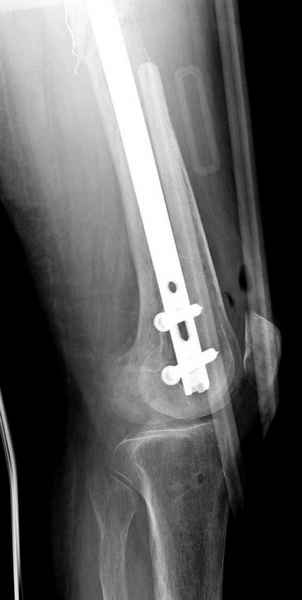

Для предупреждения кровотечения во время рассверливания, за день до операции провели эмболизацию сосудов питающий метастаз. http://radiology.rsnajnls.org/cgi/reprint/150/3/673.pdf (7-11, 12-15-16)

С минимальным рассверливанием и ретроградным методом провели остеосинтез бедра 12 мм гвоздем. (17-20)